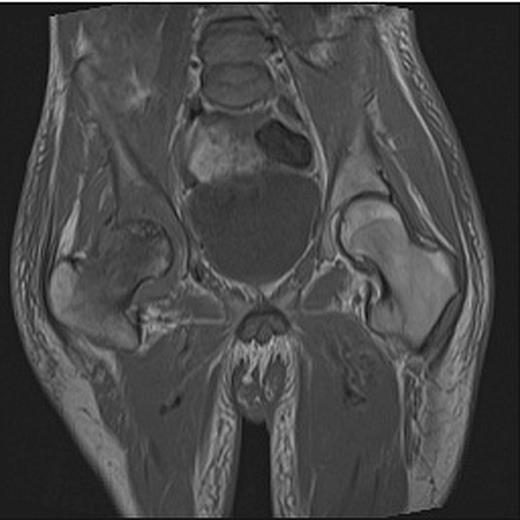

At presentation the patient was afebrile and haemodynamically stable. He was assessed by both the medical and surgical teams at a district general hospital and commenced on intravenous metronidazole and flucloxacillin for a presumed groin abscess. On examination, a pansystolic murmur was heard across precordium with no peripheral stigmata of endocarditis and a discharging sinus in the right groin with a grossly limited range of movement of the right hip. Blood tests revealed a white cell count (WCC) of 7.1 (neutrophils 5.8) and C-reactive protein (CRP) of 146. A pelvic radiograph revealed evidence of degenerative change in the right hip (Fig. 1) and following review by the local orthopaedic team an MRI was carried out confirming avascular necrosis of the right femoral head with an associated collection (Fig. 2).

Pelvic X-ray showing joint space narrowing and collapse of the right hip.